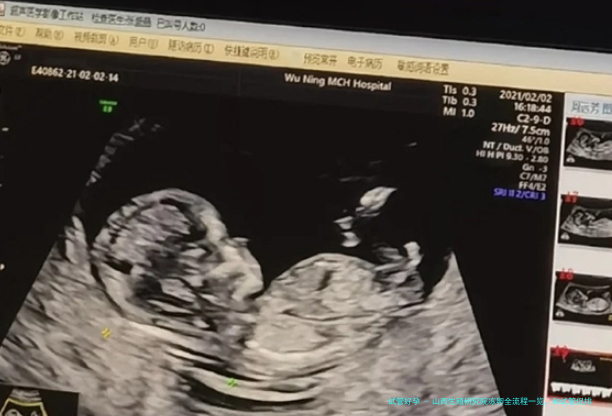

其实卵子冷冻保存即是将母体中健康的卵子取出来冷冻,使卵子不会老化。当女性要想怀孕时,就可以这一些卵子进行受精。但是在我国卵子冷冻保存的要求相比严格,契合卵子冷冻保存的先决条件才能申请。而且卵子冷冻的步调相较复杂,需要进行前期检查,促排卵等,打算去卵子冷冻保存的女性一定要思索清晰。

冻卵前检查:在冻卵前,女性需要做一个详细的身体检查。因为有些女性身体内会存在一些病毒感染。提前了解女性的身体,有助于冻卵的成功;促排卵治疗:在检查结束之后,医生会根据患者的实际检查结果制定促排卵方案。医生会开促排卵药物,以此来促进多个卵泡发育,增加取卵个数,这个时间段一般会持续1-2周。女性的身体素质不同,促排卵药物的使用率也会不同。冻卵的成本也会发生变化;取卵:在卵子发育到一定大小之后,医生会根据患者的实际身体情况来决定取卵的时间。取卵的时候,医生会用专业的取卵针将卵泡吸瘪,然后取出卵子。由于取卵后有可能会出现腹水的症状,因此患者可以多和冬瓜水和脉动,此外,也要注意防止卵巢过度刺激的出现;冻卵保存:卵子取出后,卵子需要立即进行处理,保存在超低温环境中。现如今一般采取的是玻璃化冷冻方法。山西有很多可以冻卵的医院,不同医院的收费标准和成功率都不一样。所以在选择冻卵医院之前需要综合考虑。Tips: